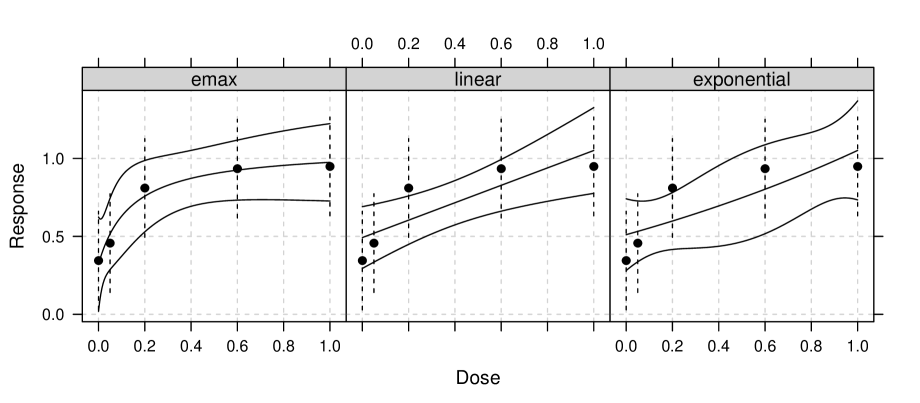

Fitting the dose-response models with the necessary parameter constraints can be done using the fitMod function from the DoseFinding R package. The fitted dose-response functions are shown in Figure 5

The parameter estimates of the models can be found in Table 1, in addition to the p-values for testing versus , for each of the three models. It can be seen that the p-values for the models, considering all three models as candidate set, are all smaller than . Of course, this is also true for the p-values that result from considering each model class separately.

| Model | Parameter estimates | test-statistic | p-value∗ | p-value∗∗ |

|---|---|---|---|---|

| Emax () | 0.335 | 0.001 | 0.001 | |

| Linear | 0.287 | 0.006 | 0.002 | |

| Exponential () | 0.276 | 0.009 | 0.004 |

For comparison we will also apply the MCP-Mod procedure. Similar to Bretz et al. (2005), we choose an Emax shape with , a linear shape and two exponential shapes, one with and the other with . The candidate shapes of the MCP-Mod procedure are presented in Figure 4 (c). The results shown in Table 2 have been calculated using the MCTtest function in the DoseFinding package. One can see that the Emax and linear model have p-values similar to the LR test. However, the two exponential shapes have p-values , despite the fact that a trend could be detected using the LR test for the exponential model. The reason is that neither of the two values fits the data well. If the exponential model for would have been included in the set of MCP-Mod candidates also a p-value smaller than would be observed.